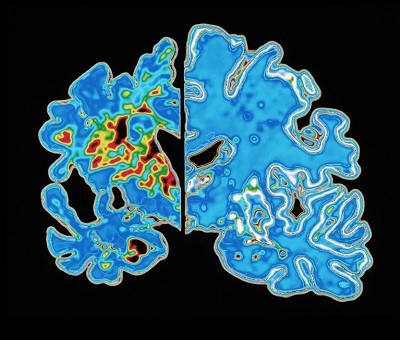

They found that young and old adults with healthy cognition generated neurons, a process called neurogenesis, at high levels for their age. The team estimated that the new neurons made up only a small fraction — 0.01% — of those in the hippocampus, a brain region that’s essential for memory. By contrast, in people experiencing cognitive decline, including individuals with Alzheimer’s disease, neurogenesis seems to falter: the researchers spotted fewer developing, or immature, neurons in those brain samples.

Surprisingly, a group of ‘super agers’ had an even higher number of immature neurons than did other groups, and significantly more than did those with Alzheimer’s. However, the group sizes were small, so the findings were not all statistically significant.